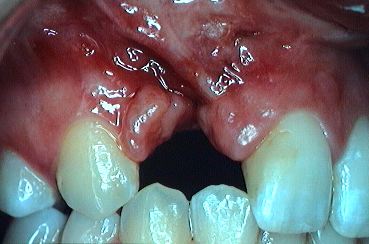

Avant l'intervention, il faudra déterminer si un traitement orthodontique préliminaire est nécessaire. S'il l'est, c'est en général à cause de la présence d'un articulé dentaire croisé: on voit (Fig.4) les dents de l'arcade supérieure (du côté de la fente) s'articuler à l'intérieur (flèches) par rapport aux dents de l'arcade inférieure.

L'articulé croisé résulte d'une croissance de l'arcade supérieure insuffisante dans le sens transverse (en largeur). Cette insuffisance est causée par la présence de tissu cicatriciel. Ce tissu cicatriciel constitue l'une des séquelles des premières opérations de fermeture de la fente durant la prime enfance (Fig.5, zone cerclée en noir).

Ces cicatrices sont responsables de tensions sur le palais durant son développement. La croissance du palais peut en être plus ou moins affectée (ralentie), suivant l'ampleur de ces tensions cicatricielles. Un articulé croisé en est, souvent, la conséquence dentaire.